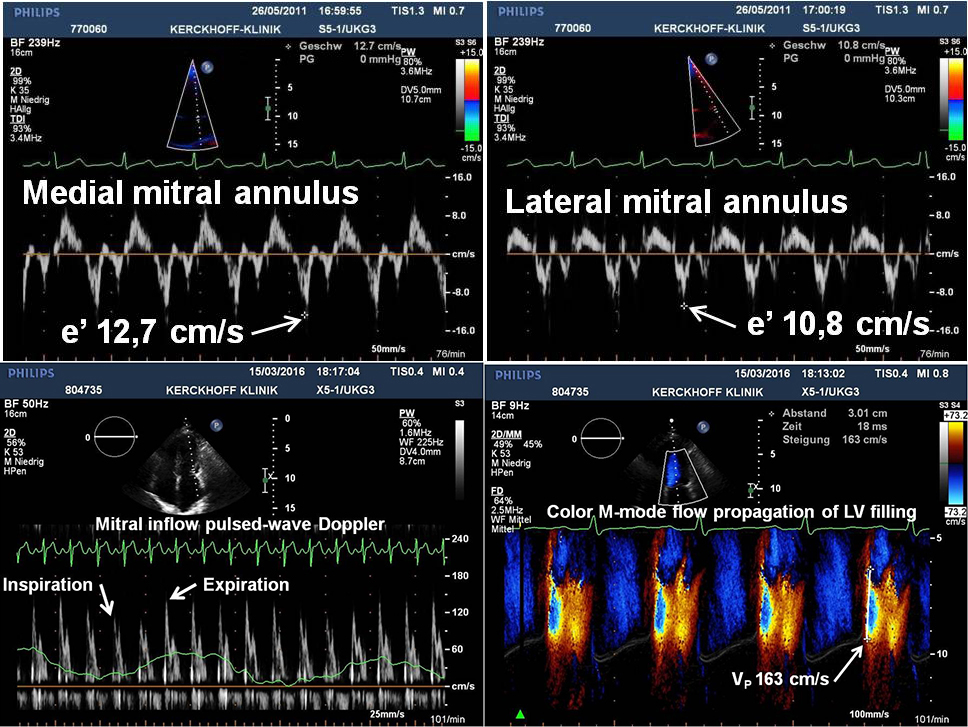

Baseline 2D echocardiography often shows a hyperdynamic mitral annulus with exaggerated motion in patients with CP [12]. This phenomenon may be recognised with the naked eye on greyscale images, but is better appreciated by tissue Doppler imaging. In general, a mitral annular e’ velocity 38 cm/s represents a discrete amplitude cut point to distinguish CP from RCM, possibly due to a greater contribution by the longitudinal movement of the left ventricle for diastolic filling and normal LV relaxation [13,14]. Also, due to the tethering of the adjacent fibrotic and scarred pericardium, which influences the lateral mitral annular translocation in patients with CP, the lateral e’ velocity is lower than the medial e’ velocity, a phenomenon termed annulus reversus [15], which is present in up to 75% of surgically proven CP [16].

There is an inverse relation between the ratio of early transmitral to annular velocities (E/e’) and LV filling pressures (annulus paradoxus and E/e’ ratio should not be used to estimate LV filling pressures in patients with CP). The plausible explanation for this finding is the exaggerated longitudinal motion of the mitral annulus, despite high filling pressures [18]. As a secondary measure, colour M-mode flow propagation of LV filling may aid in the differential diagnosis between CP and RCM. The inflow velocity of the first aliasing is usually normal or markedly increased (usually >100 cm/s) in CP, but significantly lower in RCM [13].

Recently, a multifaceted algorithm with five key echocardiographic findings, including respiration-related ventricular septal motion, mitral inflow pattern, medial (septal) mitral annular e’ velocity, and hepatic vein expiratory diastolic flow reversal has been proposed that is also applicable to patients in atrial fibrillation [19]. Key echocardiographic features are listed in Table 1 and typical Doppler findings are displayed in Figure 1.

Figure 1. Typical Doppler findings from a patient with surgically proven constrictive pericarditis. Medial (upper left) and lateral (upper right) mitral annulus early diastolic (e’) velocities by tissue Doppler show a preserved longitudinal function and reversal of the usual relationship (so-called annulus reversus). Pulsed-wave Doppler spectrum of mitral inflow velocities (lower left) demonstrates a marked respiratory variation of the peak E-wave velocity. Colour Doppler M-mode flow propagation of left ventricular (LV) filling (lower right) illustrates a steep slope (163 cm/s) of the first aliasing velocity contour (white line).